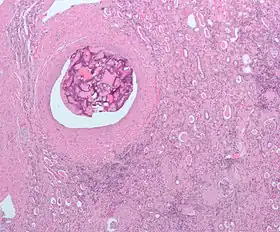

| Micrograph of embolic material in the artery of a kidney. The kidney was surgically removed because of cancer. H&E stain. | |

An embolism is the lodging of an embolus, a blockage-causing piece of material, inside a blood vessel.[1] The embolus may be a blood clot (thrombus), a fat globule (fat embolism), a bubble of air or other gas (gas embolism), amniotic fluid (amniotic fluid embolism), or foreign material.